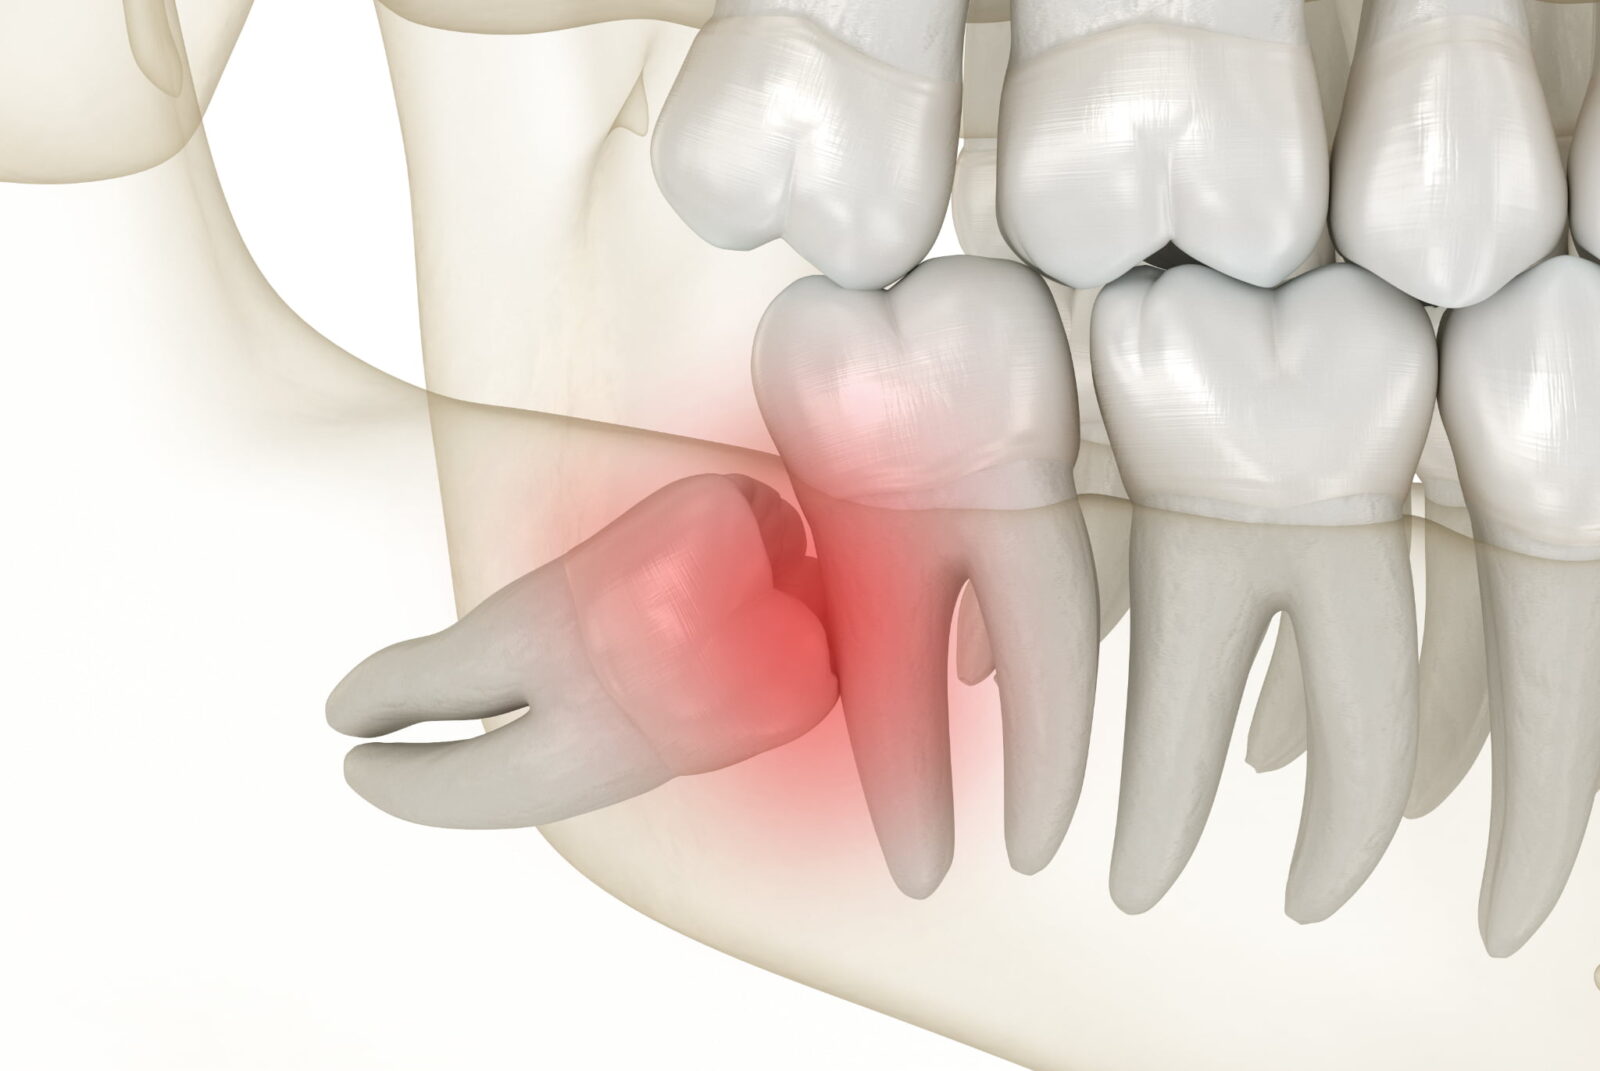

親知らずは最後に生えてくる永久歯で、横向きに生えるケースも少なくありません。横向きに生えた親知らずは、歯並びや噛み合わせに悪影響を与えることがあるため、抜歯が推奨されるケースも多いです。

現代人の食生活はやわらかいものが増え、よく噛む習慣が減ったことで、顎の骨が十分に発達しにくくなっています。その結果、親知らずが生えるためのスペースが足りず、奥歯にぶつかるように横向きに生えることがあります。

本来なら親知らずがまっすぐ生えるためには、ある程度の余裕が必要です。しかし、そのスペースが足りないと、歯が行き場を失って横や斜めに向かって生えてしまうのです。

横向きに生えている親知らずは、抜歯が必要とされるケースが多いです。なぜなら、横向きに生えた歯は歯ぐきの中に埋まったままだったり、一部だけ顔を出していたりすることが多く、周囲の歯や歯ぐきに悪影響を与えることがあるからです。

虫歯や歯周病を繰り返したり、痛みや腫れがあったりする場合は、抜歯を検討することが多いでしょう。

隣の歯に悪影響を及ぼす可能性がある

横向きに生えた親知らずが隣の歯に強く押し当たることで、手前の歯の根元に強いダメージを与える可能性があります。この圧力によって歯が移動したり、歯並びが乱れたりすることもあります。また、歯の根に炎症が起きる可能性もあり、隣の健康な歯まで治療が必要になるケースも少なくありません。

横向きに生えた親知らずは歯ぐきの中に埋まっていたり、一部だけが見えていたりすることが多く、その周囲には細菌がたまりやすい状態になります。このような状態が続くと、歯ぐきが炎症を起こして腫れる智歯周囲炎という症状につながります。

智歯周囲炎が起こると、痛みを感じたり、口が開きにくくなったり、場合によっては発熱を伴ったりすることがあります。炎症が繰り返されることで、親知らずの周囲に膿がたまり、膿瘍(のうよう)を形成するケースも考えられます。